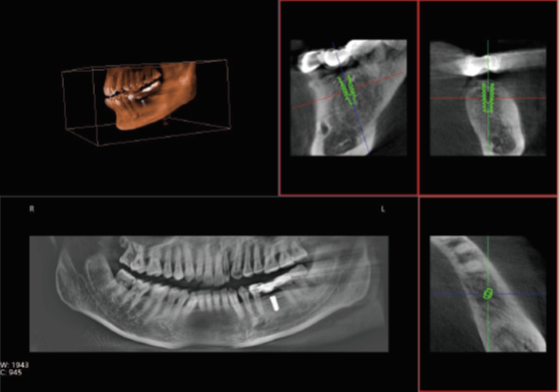

眾所周知,在口腔內種植牙齒是十分精細的手術,沒有先進的可視化影像設備支持的種植牙手術,就猶如盲人摸象,手術效果難以預知??谇籆T影像能測量牙槽骨的高度和寬度,估計種植部位,與下頜阻生磨牙相關的低位下牙槽神經管影響頜骨的疾病的病理學評估。

口腔CT圖像

正常情況下,牙齒的排列不在一個平面上, 且具有一定的生理弧度,普通X線往往使圖像相互重疊,使圖片看不清楚。但是,口腔CT的三維成像對牙體、牙根、牙周膜等微細結構顯示更加清晰。可以幫助醫(yī)生了解斷根,牙根內吸收、根管鈣化、牙根結石、牙槽骨退縮等情況,能用于根管治療前尋找根管,術后評估根管充填情況,評估牙周炎程度及預期治療效果等。